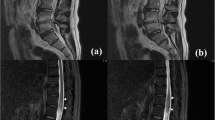

Four individuals (n = 4, 3 men and 1 woman, mean age 58.25 years [range 56–61]) completed inpatient rehabilitation during the COVID-19 pandemic. All presented after COVID-19 infection and were admitted to acute care with progressive paraparesis. None were able to ambulate on admission to acute care. All received extensive evaluations which were largely negative except for mildly elevated CSF protein and MRI findings of longitudinally extensive T2 hyperintensity signal changes in the lateral (n = 3) and dorsal (n = 1) columns. All patients experienced incomplete spastic paraparesis. All patients experienced neurogenic bowel dysfunction; a majority experienced neuropathic pain (n = 3); half experienced impaired proprioception (n = 2); and a minority experienced neurogenic bladder dysfunction (n = 1). Between rehabilitation admission and discharge, the median improvement in lower extremity motor score was 5 (0–28). All patients were discharged home, but only one was a functional ambulator at time of discharge.

Huang HY, Shah LM, McNally JS, Sant T, Hutchins TA, Goldstein ED, et al. COVID-19-associated myelitis involving the dorsal and lateral white matter tracts: a case series and review of the literature. AJNR Am J Neuroradiol. 2021;42:1912–7.